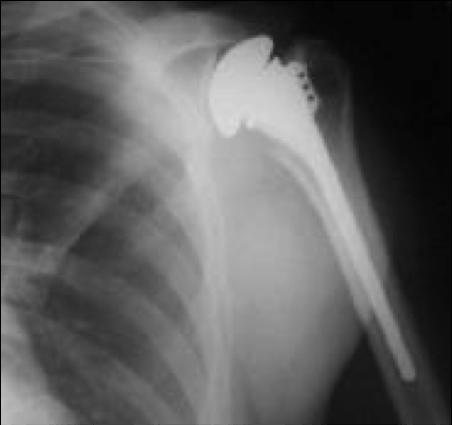

위의 사진과 같이 기존의 인공관절은 humerus 의 골두를 제거하고 glenoid 모습과 비슷하게 작동하는 원리로 인공관절이 되었으나 최근에는 humerus head 의 medialization 효과와 deltoid muscle lever arm의 증가로 더 효과가 있는 reverse shoulder arthroplasty 가 많이 시행되고 있습니다. 1990년대부터 수술을 시작했으니 30년 정도 지난 수술법입니다.